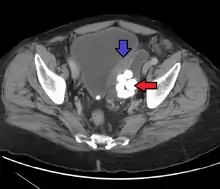

Diverticulum of urinary bladder of a 59-year-old man, transverse plane

Bladder diverticula containing stones. Also note that the bladder wall is thickened due to possible transitional cell carcinoma.- Bladder diverticula as seen on ultrasound with doppler[18]

- Bladder diverticula as seen on ultrasound[18]